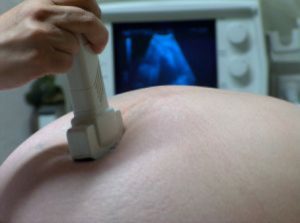

Te recostarán en una camilla con el vientre descubierto desde la parte más baja. Para mejorar el contacto entre el transductor y la superficie del abdomen te aplicarán un gel o aceite.

En ocasiones es necesaria una exploración a través de la vagina para intentar obtener imágenes más nítidas. Para ello utilizan una sonda diseñada especialmente, la incomodidad de esta exploración es similar a la de un tacto vaginal.